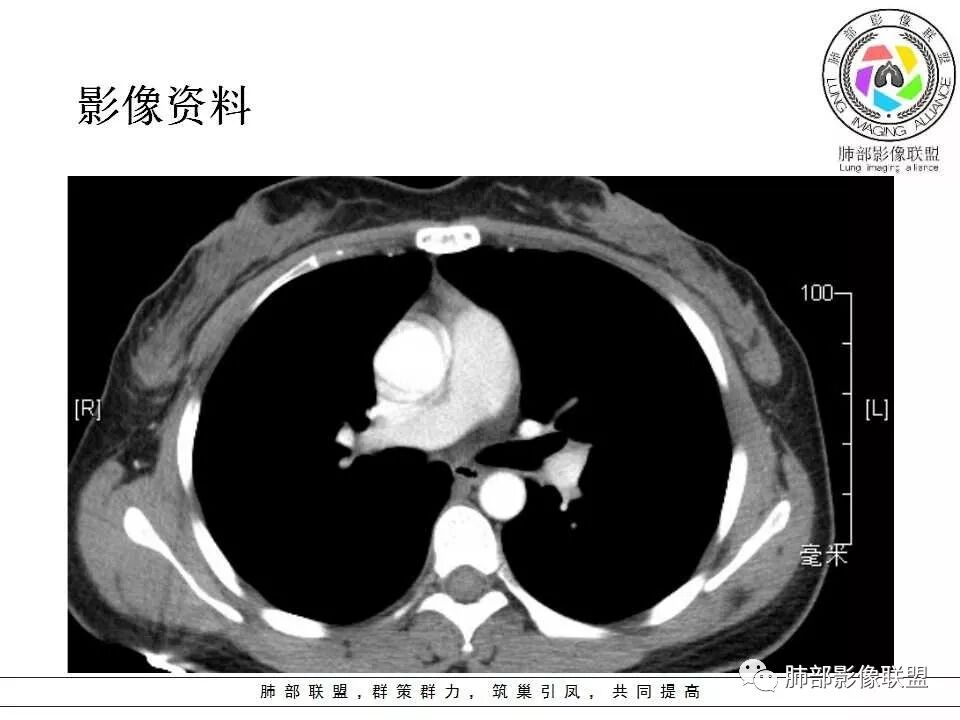

患者中年女性,发现左肺上叶占位,随访发现体积增大。胸部CT:左肺上叶尖后段实性占位,位于支气管旁,未见支气管阻塞,病灶边界清楚,边缘光滑,增强可见病灶均匀强化,血管贴边,考虑良性病变,PSP?

患者中年女性,发现左肺上叶占位1年余入院,随访发现体积增大。胸部CT:左肺上叶尖后段近肺门及叶间裂实性类圆形结节,病灶边界清楚光滑,增强可见病灶明显均匀强化,其旁未见支气管堵塞。综合考虑良性病变,孤立性纤维瘤可能,鉴别巨大淋巴结增生症及硬化性肺细胞瘤。

中年女性,发现左肺上叶占位。胸部CT:左肺上叶尖后段孤立卵圆形实性病灶,位于支气管旁,边界清楚,边缘光滑,血管贴边,肺动脉为主征,增强扫描明显均匀强化。考虑:PSP?鉴别CD、类Ca。

左肺上叶类圆形实性病灶,边缘光滑,可见血管贴边征,病灶与左肺上叶支气管关系密切,左肺动脉相对增粗,增强病灶均匀强化,常规考虑PSP,其次神经内分泌肿瘤不排除。

年轻女性,左肺门肿块,边缘光滑,密度较均匀,增强后肿块明显均匀强化,血供丰富,病史提示一年明显增大,也说明富血供,常规考虑PSP,类癌待排。

36岁女性,发现左肺占位1年,时有干咳。CT:左肺门(上叶尖后段?)类圆形结节,边界清,靠前边缘似有GG0,近肺门侧与血管密切接触,似有小凸起,增强见明显均匀强化,似有条片状影往肺门侧血管钻。图片有点少,病灶与支气管的关系看不清(目前的图片与支气管不密切)。随诊结节增大,整体考虑典型类癌可能性大,鉴别硬化性肺细胞瘤。

3.1单发型CD的肺部表现

单发型CD多为透明血管型,所以明显强化和中央分枝状钙化具有特征性。在CT上表现圆形或类圆形软组织密度影,伴或不伴周围淋巴结增生,体积一般较大,边缘光整,病灶中央的弧形、线样、分枝样及枯枝样钙化(因为肿块内增生的血管组织玻璃样变或退变后钙盐沉积,故多呈血管样铸型的分支状或枯枝状);透明血管型因为其内血供丰富,周围可见粗大的供血动脉,在多期扫描动脉早期明显强化,强化程度与大血管相仿,又由于病灶内血管壁玻璃样变或纤维化及内皮细胞过度增生致血管腔狭窄,对比剂退出减慢,故延迟扫描扫描仍可持续强化,呈“早进晚出”的强化方式。因为其血供丰富,坏死、囊变或出血少见,但是有时候病灶内灶状或条片状低密度影,是纤维组织或发生玻璃样变性的血管结构,而不是缺血坏死区。